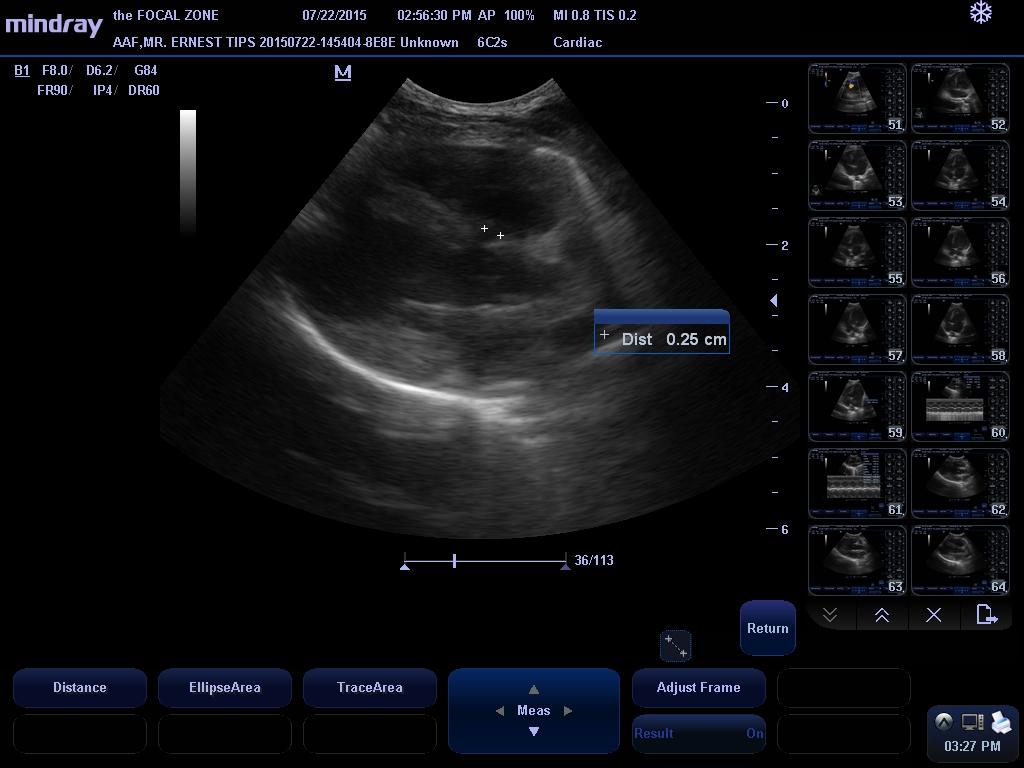

VSD Vmax – 4.9 m/s

VSD diam – 2.5 mm

This examination demonstrates a small left to right shunting perimembranous ventricular septal defect with very mild left heart volume overload. The clinical significance of VSDs are dependent on the size of the defect and resistance to flow, which is related to the left and right ventricular systolic pressures. With small defects, there is a high resistance to systolic flow, and thus, there is only a small amount of blood that shunts through the defect, whereas with larger defects, there is a significant amount of shunting that can eventually lead to left-sided congestive heart failure and even shunt reversal if secondary pulmonary hypertension develops. This patient’s VSD appears to be small, and more importantly, his shunt velocity is consistent with a restrictive defect, indicating that the small size of the detect provides high resistance to flow, so that while his murmur is very loud, there is actually only a small volume of blood shunting from the left ventricle to the right ventricle (the loud murmur is caused by the blood squeezing through a small opening). Given the presence of a restrictive defect, it is possible that the VSD may never become clinically relevant, though the presence of mild left heart dilation suggests that his disease must be monitored carefully over time.